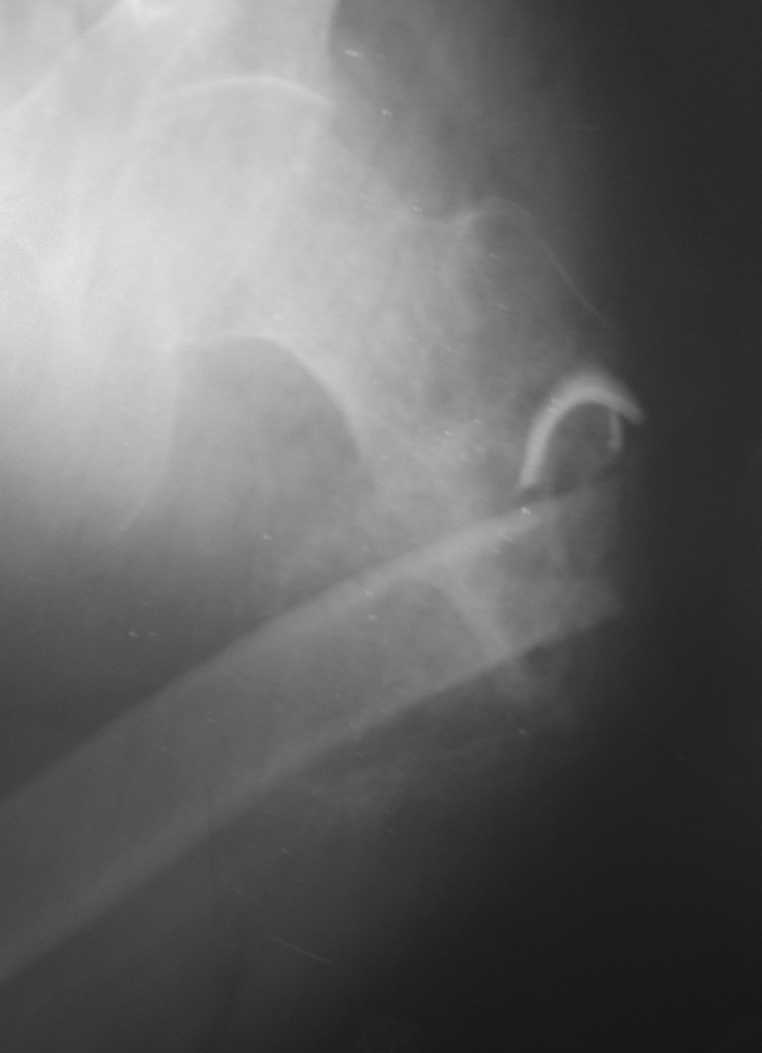

Неправильно консолидирующийся перелом бедра |

Пациент 34 лет бомж получил травму окло 1,5-2 мес назад. За мед помощью не обращался. При поступлении левая нижняя конечность резко ротирована кнутри, варусная деформация бедра. По наружной поверхности рана 2 на 2 см с незначительным серозно гнойным отделяемым,умеренными грануляциями, в ране дистальный отломок бедреной кости. Патологическая подвижность в области перелома назначительная. Проведена попытка репозии дистракционным аппаратом, с незначительным эффектом (несколько уменьшилась внутренняя ротация.Что делать дальше? Остеотомия? Санация гнойного очага